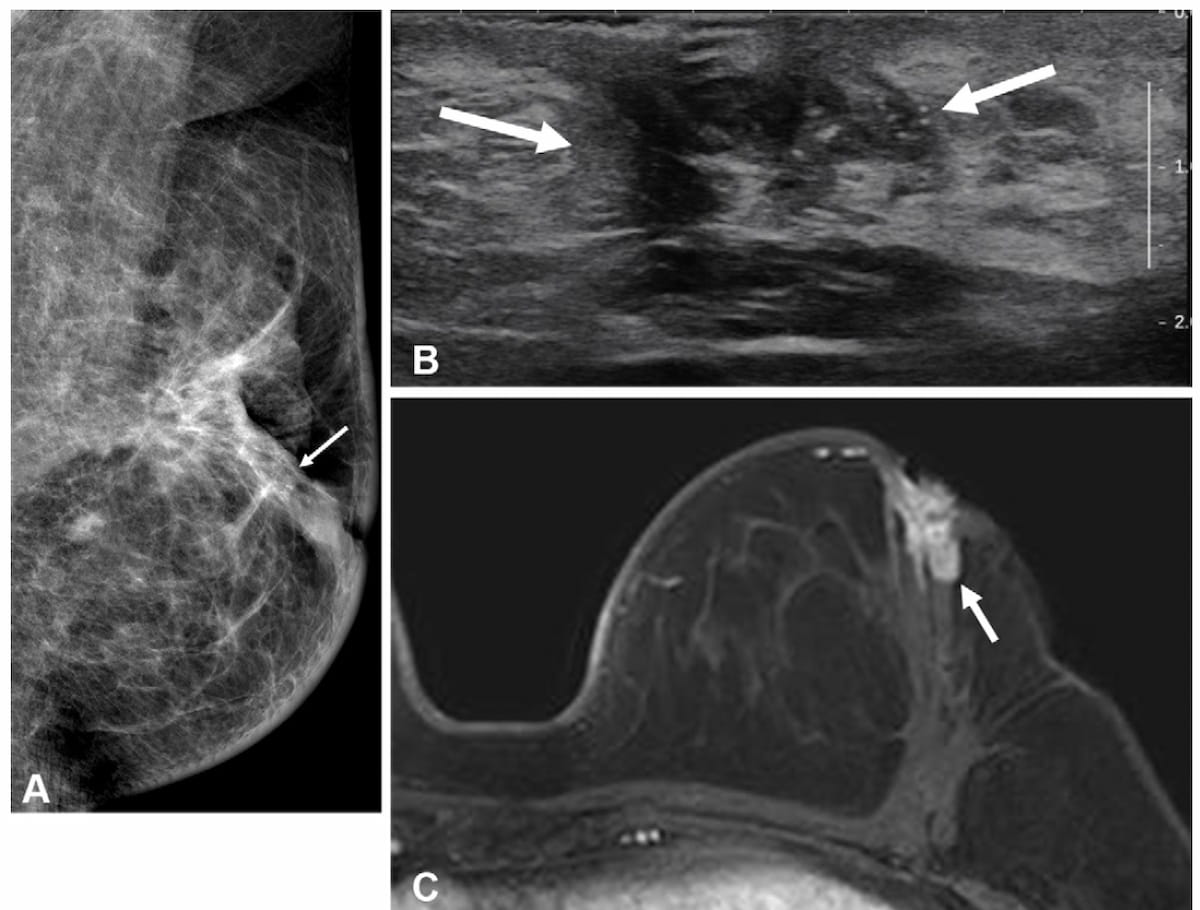

For HER2-positive breast cancer patients with radiologic complete response on breast MRI after neoadjuvant chemotherapy (NAC), the absence of calcifications was associated with over a 13 percent higher positive predictive value (PPV) for pathologic complete response (pCR).